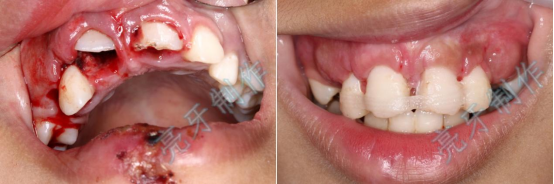

病例五:牙齿嵌入牙槽骨,牙龈撕裂,治疗后,恢复了自信和美丽的笑容。